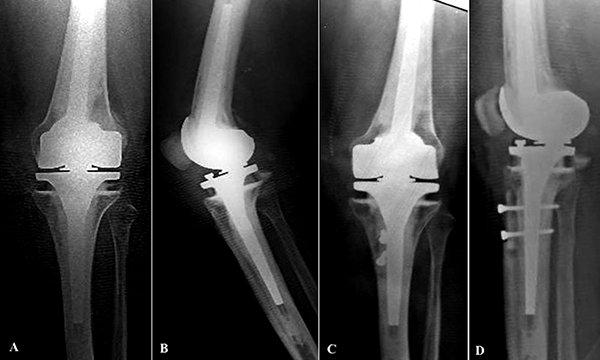

Figura 4: Caso 12. A y B) Paciente de sesenta años con implante abisagrado que presenta una inestabilidad rotuliana con múltiples episodios de luxación patelofemoral. C y D) Control postoperatorio donde se observa una osteotomía con medialización de la tuberosidad anterior de la tibia.